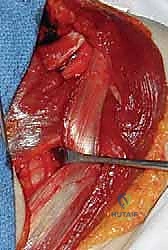

الخطوة الخامسة: نقل وتثبيت الوتر

يتم تمرير وتر العضلة الصدرية الكبرى تحت العضلة ذات الرأسين (Biceps) أو فوقها (حسب الحالة)، وسحبه نحو المنطقة العظمية المحضرة. يستخدم الدكتور هطيف أحدث الخطاطيف الجراحية (Suture Anchors) المصنوعة من التيتانيوم أو المواد القابلة للامتصاص لتثبيت الوتر بقوة هائلة في العظم.

يتم التأكد من الشد المناسب (Tensioning)؛ فإذا كان الوتر مشدوداً جداً قد يتمزق، وإذا كان مرتخياً لن يؤدي وظيفته. هذه الخطوة تتطلب "حسّاً جراحياً" لا يتوفر إلا لجراح متمرس مثل الأستاذ الدكتور محمد هطيف.

الخطوة السادسة: الإغلاق التجميلي

بعد التأكد من استقرار المفصل والحركة الميكانيكية السليمة، يتم إغلاق الجرح بطبقات متعددة باستخدام خيوط تجميلية لتقليل الندبات الجراحية إلى الحد الأدنى.